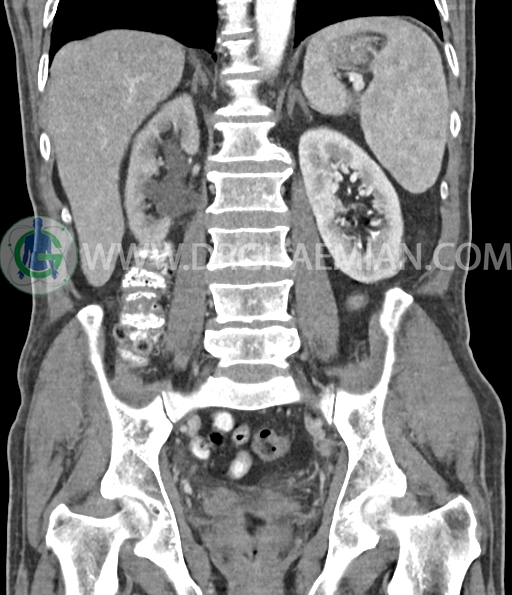

سی تی اسکن لگن و شکم از تشعشعات برای ایجاد تصاویر عرضی مقطعی از لگن و شکم استفاده می کند. در این کیس سرطان سلول انتقالی کلیه، ضایعه کبدی، دیورتیوکولوز، کیست کورتیکال در کلیه چپ، پروستات بزرگ شده، افزایش ضخامت دیواره مثانه دیده می شود.

در سی تی اسکن اسپیرال شکم و لگن با و بدون کنتراست خوراکی و وریدی (مولتی دیدکتور 16 با مقاطع ظریف و بازسازی های ساژیتال و کرونال) :

کیست کورتیکال به قطر 15mm در پل تحتانی کلیه چپ دیده می شود.

پروستات با دیامتر عرضی 60mmبزرگ تر از نرمال، همراه با bulging لوب مدین به کف مثانه رویت شد.

افزایش ضخامت جداری مثانه مشهود است.

افزایش ضخامت جداری و نامنظمی و لوبولاسیون همراه باenhancement مطرح کننده انفیلتراسیون و ضایعات تومورال در سمت راست ناحیه ترایگون و دیواره لترال راست مثانه دیده می شود که باعث اتساع حالب راست و هیدرونفروز moderate در کلیه راست شده است . این یافته های می توانند مطرح کننده TCC باشند .fat stranding در اطراف مثانه مشهود است. بیرون زدگی توده مانند به قطر 18mm در سمت راست ناحیه ترایگون دیده می شود که می تواند مطرح کننده گسترش اکسترا وزیکولر تومور باشد . لنفادنوپاتی با SAD=10mm درlevel ایلیاک داخلی چپ رویت شد . لنف نود دیگر با SAD= 5mm در همین ناحیه مشهود است. با توجه به این یافته ها stage احتمالی تومور T3، N1 or N2 می باشد .